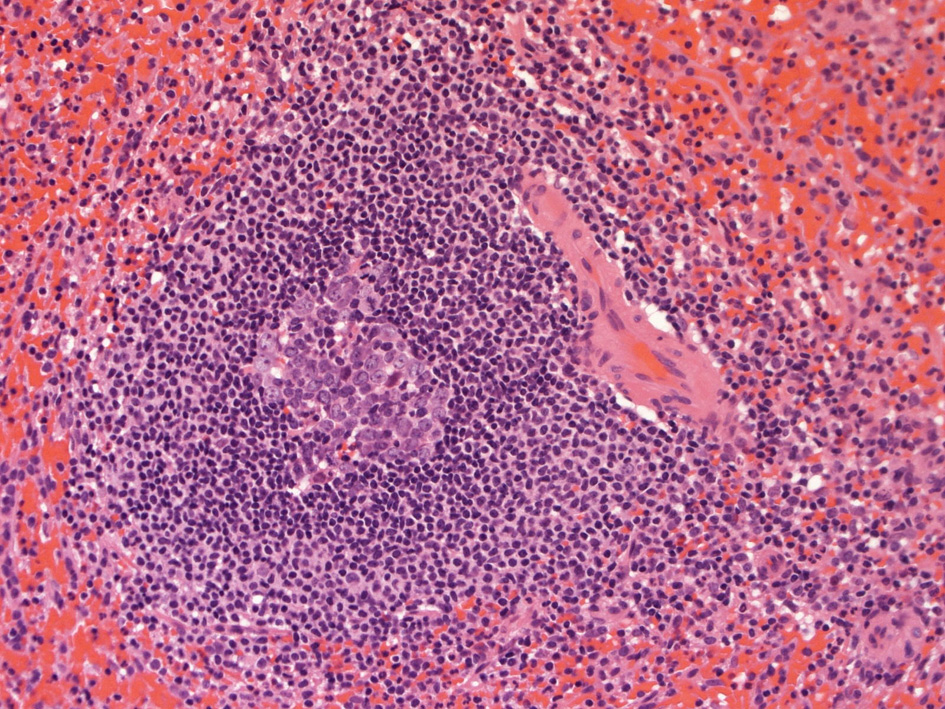

白脾髄 white pulpは中心動脈周囲に形成されているリンパ組織で, 動脈周囲リンパ鞘 periarteriolar lymphoid sheath(PALS)とリンパ濾胞(lymph follicles)の異なる2つの領域が識別される.

脾動脈脾柱という結合組織を通って実質内に入るところから毛細血管に至るところまで、その周囲にリンパ鞘(リンパ鞘=PALS/ peri-arterial lymphatic sheathの略)が形成され、所々にリンパ濾胞が発達している. 濾胞内には胚中心が見られることが多い。胚中心の周りには暗調にそまる小型のリンパ球がマントル層を作って取り囲む。リンパ鞘もリンパ節の構造と同じく粗で不規則な細網線維からできたネットワークが骨格となっている。

リンパ鞘はT細胞領域リンパ濾胞はB細胞由来です。PALSのT-cellsはCD4+ cell > CD8+ T-cells

PALS, 動脈周囲リンパ鞘 periarteriolar lymphoid sheath

リンパ濾胞

脾臓の辺縁帯は通常,よく発達した濾胞周囲領域であり,そろった/一様な核と一定量の透明な細胞質を持つ中型のリンパ球からなり,芽球が散在している。

脾臓の辺縁帯細胞はCD20+,CD79a+,IgM+,CD21+,アルカリホスファターゼ陽性であるが, CD23-,Bcl6-,IgD陰性または弱IgD+である*15

胚中心が多数出現しているときはなんらかの抗原刺激を受けたと考えられる.

慢性感染症がある人の脾臓や特発性血小板減少性紫斑病の人の脾臓では胚中心が特に発達している. 一方で自己免疫性溶血性貧血では胚中心は少なく、先天性球状赤血球症ではほとんど見られない.